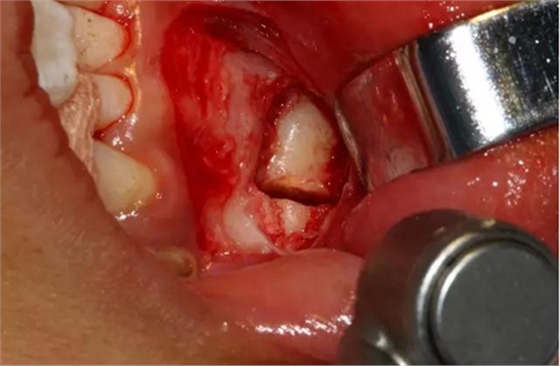

設(shè)計(jì)冠切的位置

橫斷牙冠,注意深度的把控

為了減少骨創(chuàng),“T”型分割牙冠

去除冠部

本案例要點(diǎn):1、患兒年齡小、手術(shù)的耐受性值得關(guān)注;2、阻生位置較深,麻醉的有效性很關(guān)鍵;3、埋伏阻生的位置處于下頜骨骨質(zhì)好發(fā)部位--正中聯(lián)合,所以,術(shù)中不能采用任何錘擊劈冠的力量;4、由于采用渦輪機(jī)的微動(dòng)力系統(tǒng),嚴(yán)防皮下氣腫的發(fā)生;5、術(shù)后加壓,防治水腫。